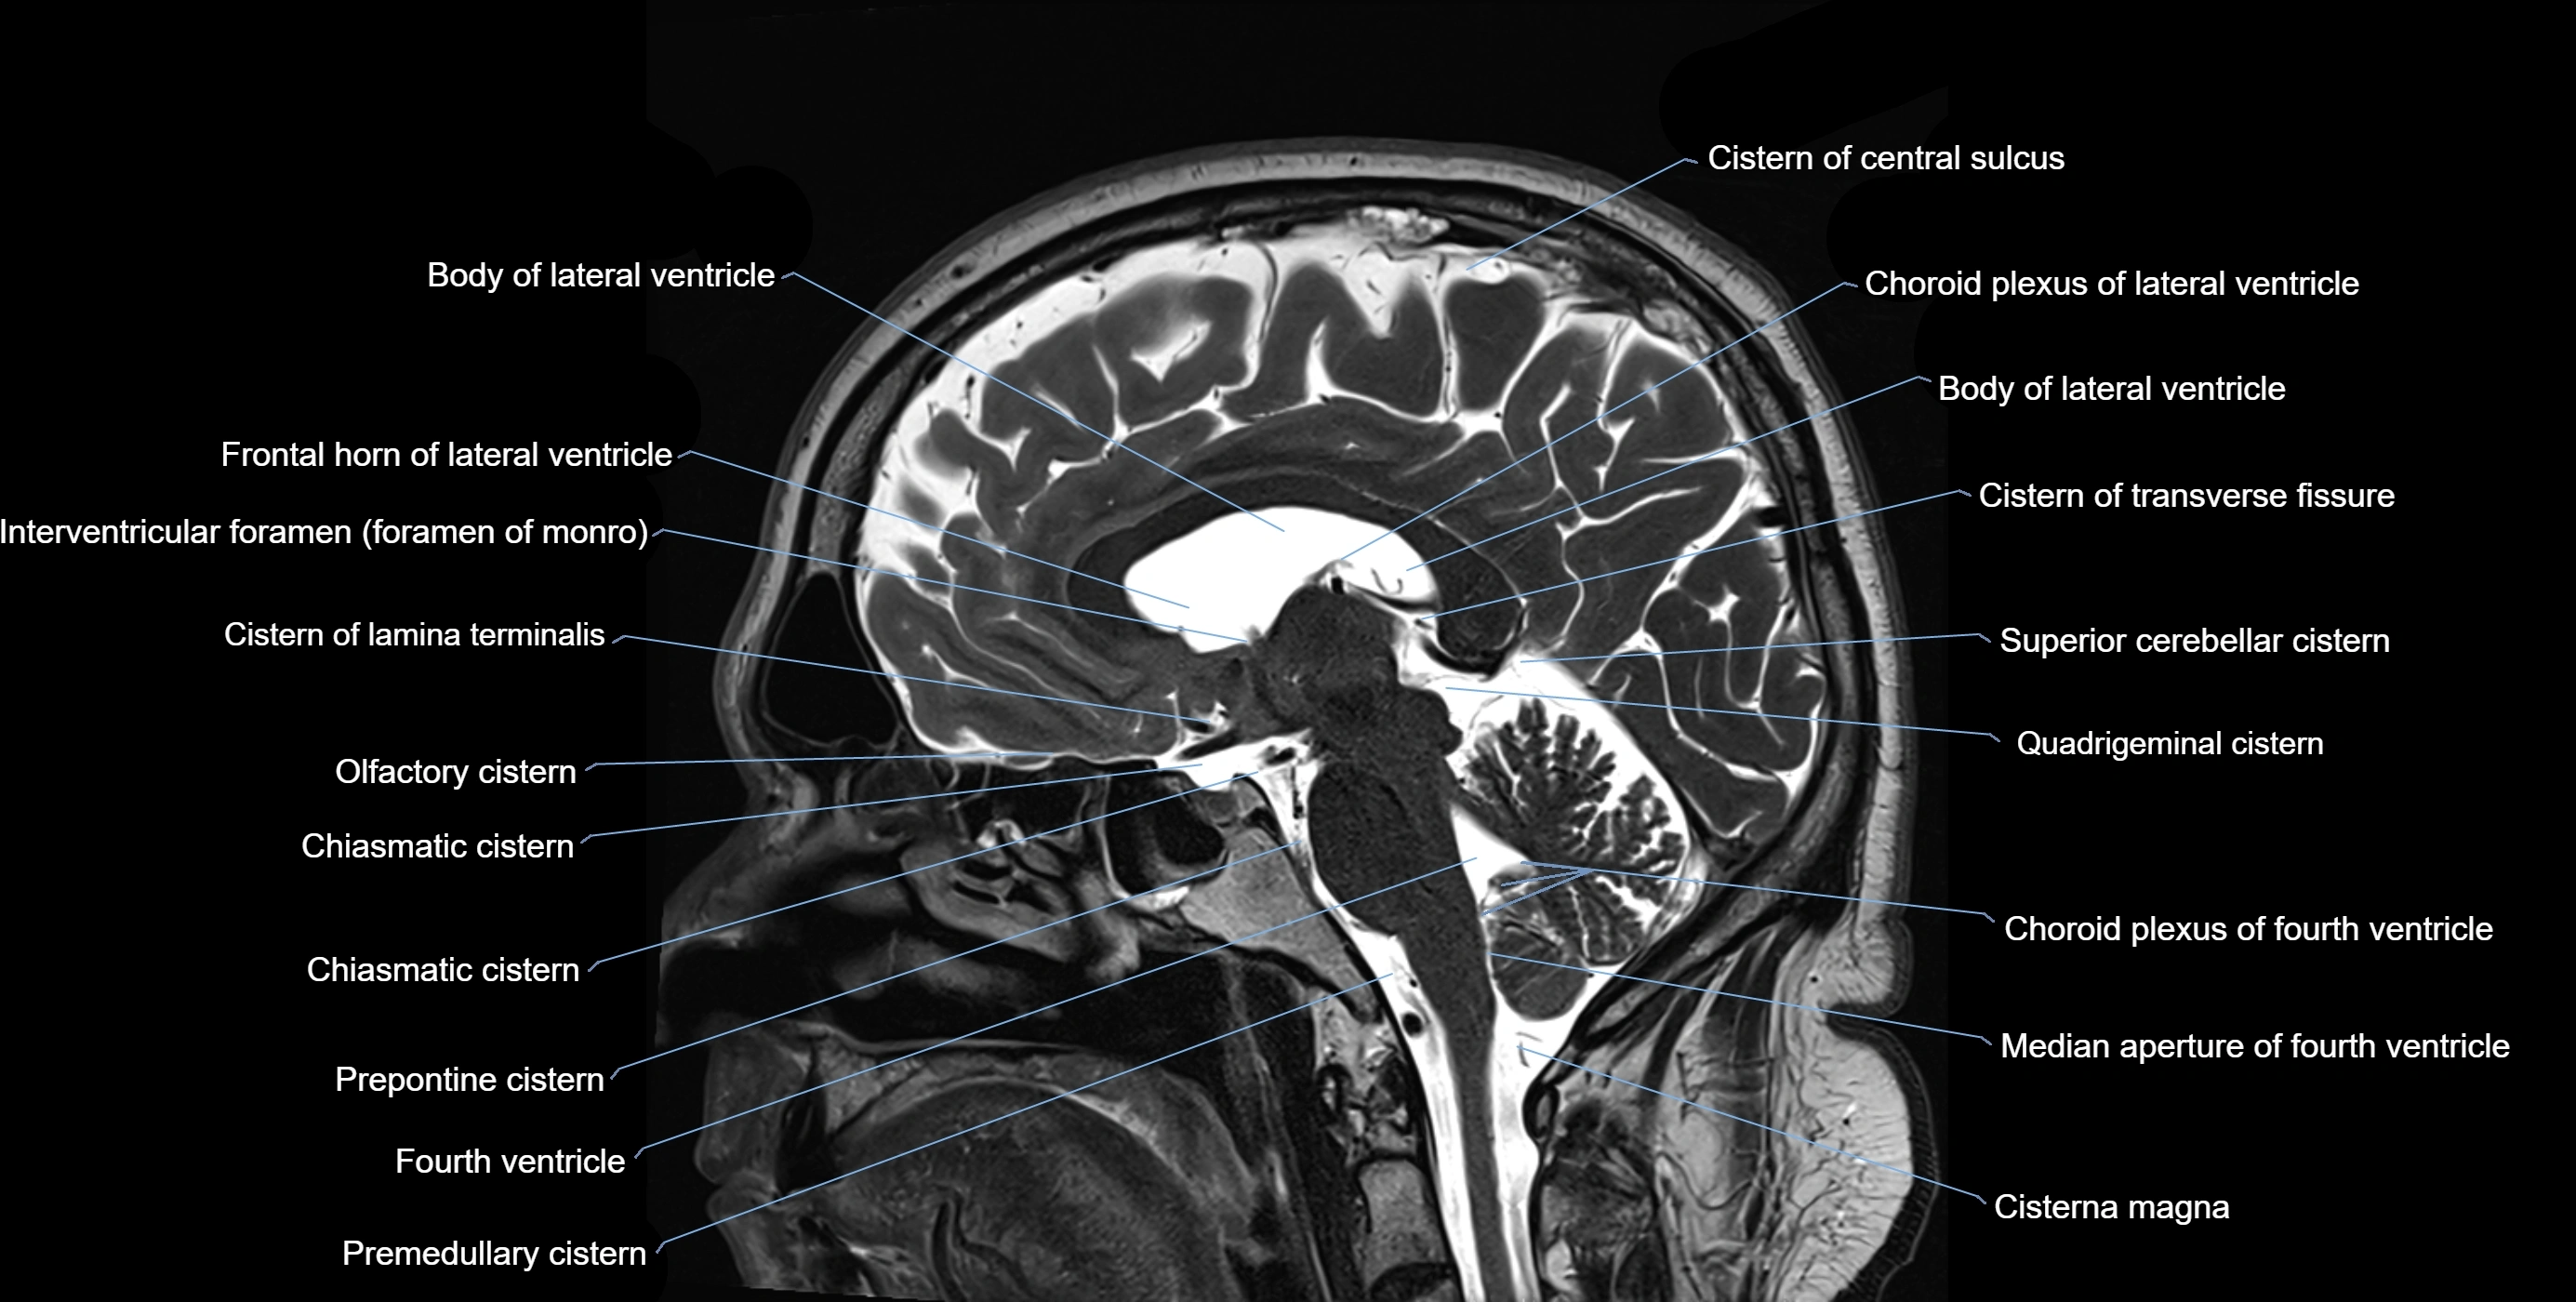

MRI images

image